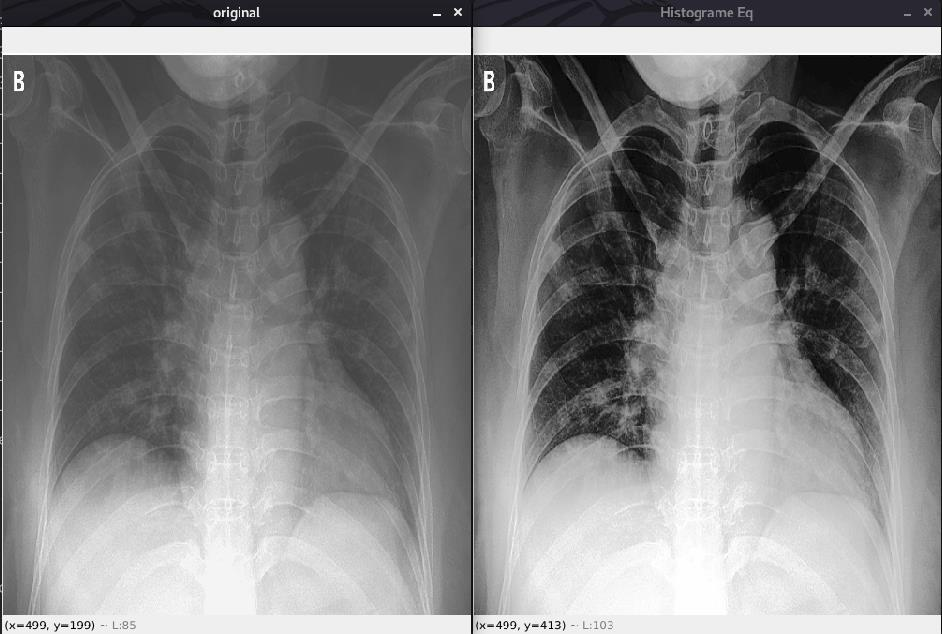

Histogram equalization is a basic image processing technique that adjusts the global contrast of an image by updating the image histogram’s pixel intensity distribution. Doing so enables areas of low contrast to obtain higher contrast in the output image. Essentially, histogram equalization works by: • Computing a histogram of image pixel intensities • Evenly spreading out and distributing the most frequent pixel values (i.e., the ones with the largest counts in the histogram) • Giving a linear trend to the cumulative distribution function (CDF)